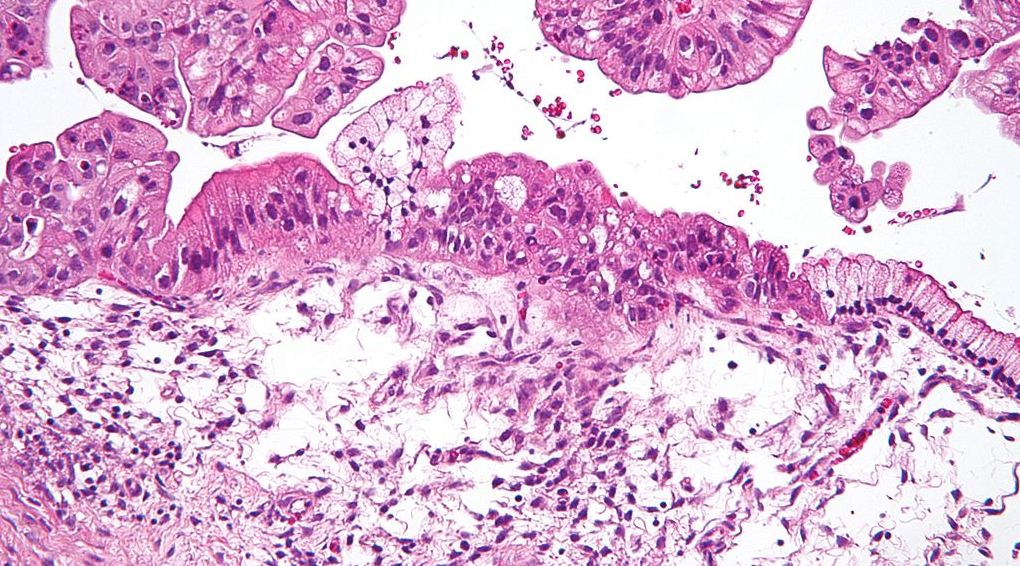

Imagen: Commons